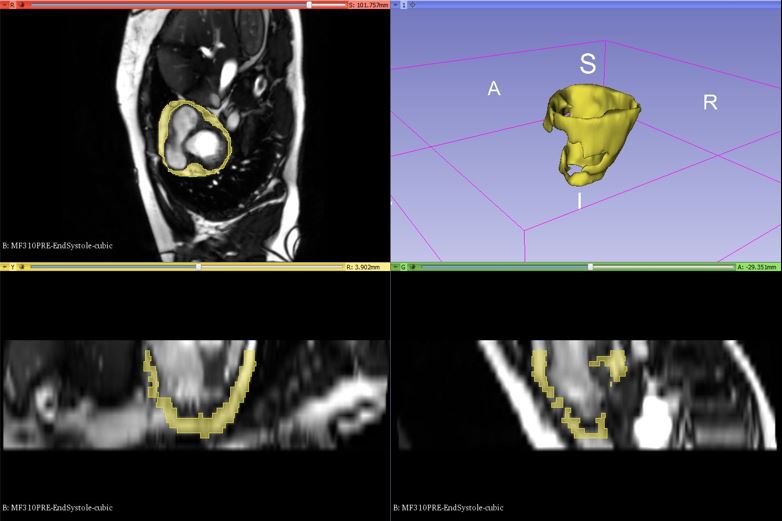

2) Identification of Epicardial Adipose Tissue

Using Echocardiography

Magnetic resonance imaging (MRI) can provide

three-dimensional (3D) assessment of EAT, but it is

expensive, time-consuming, and is only available at

large institutions.

Echocardiography is safe, real-time, inexpensive, and

can also be used to quantify cardiac structure and

function. The goal of this project is to utilize 3D

volumetric information from MRI data to develop a

shape-based model to be used in conjunction with

real-time echocardiography and advanced processing of

the radio-frequency (RF) ultrasound signals for

volumetric assessment of EAT. Machine learning

algorithms are used to differentiate tissue types based

on features from the ultrasound spectra. Leveraging the

specific individual strengths of MRI and

echocardiography has the potential to yield a more

powerful, yet less expensive analysis tool suited for

large studies of intervention and their effect on EAT

and cardiovascular health.